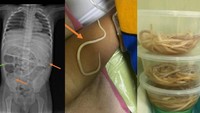

Seorang anak laki-laki (3) di Madura, Jawa Timur, datang ke Rumah Sakit Umum Soebandi dengan keluhan konstipasi atau sembelit dan perut kembung selama tiga hari. Sehari setelah dirawat, pasien mengeluh perut tidak nyaman dan kembung. Pada hari pertama observasi di rumah sakit, pasien muntah cacing dan diagnosis askariasis. (Foto: Journal of Medical Case Reports).